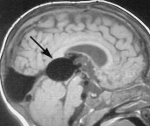

Компьютерная томография и МРТ также широко используются в диагностических целях. На снимках можно визуализировать патологические клубки эмбриональных сосудов. Для дальнейшего планирования тактики лечения необходимо проведение ангиографии, которая позволяет установить топографические отношения с нормальными сосудами и обнаружить другие возможные сосудистые аномалии. Заподозрить тромбоз можно по результатам ангиографии, поэтому контрастное рентгенологическое исследование сосудов остается основным в диагностике аневризмы вены Галена. Именно данный метод позволяет сосудистым хирургам планировать тактику оперативного вмешательства.